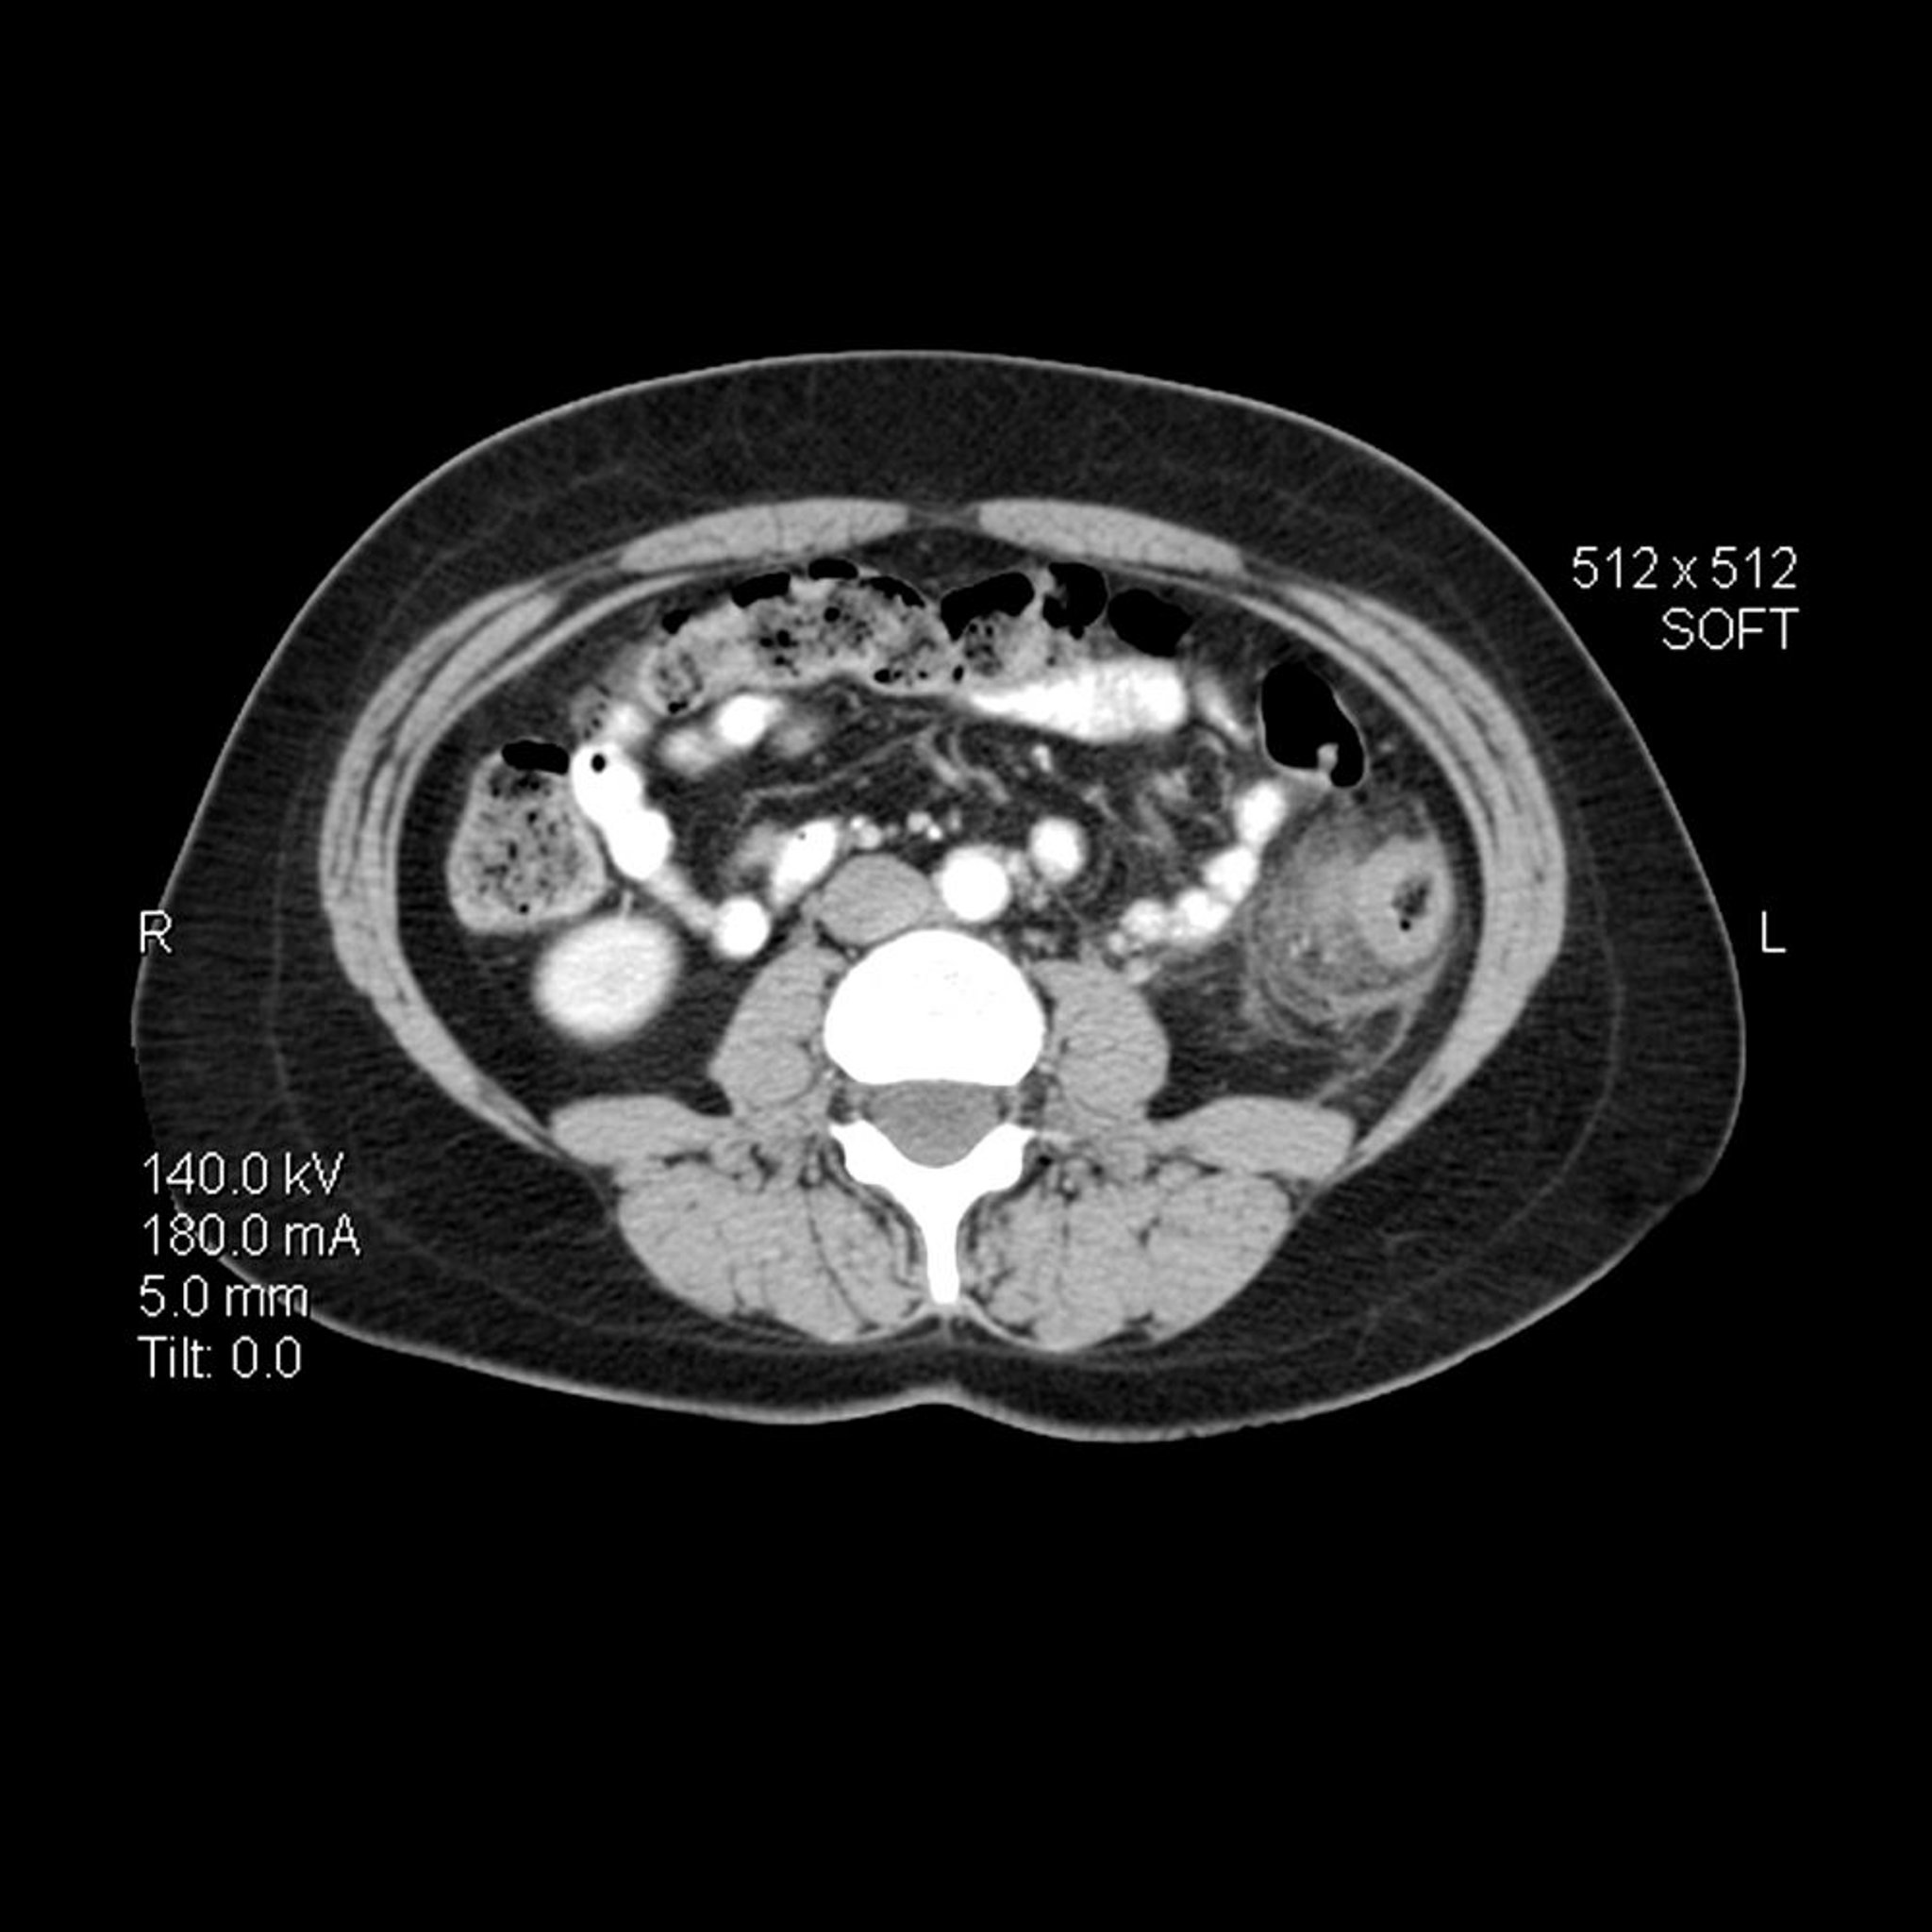

Divertikulitis (CT)

Bei diesem axialen (Querschnitts-) CT-Bild des Abdomens bei einer Person mit Divertikulitis ist die Wand des Colon descendens verdickt. Es gibt auch eine entzündliche Streifenbildung mit erhöhter Dichte in dem benachbarten Perikolonfett.